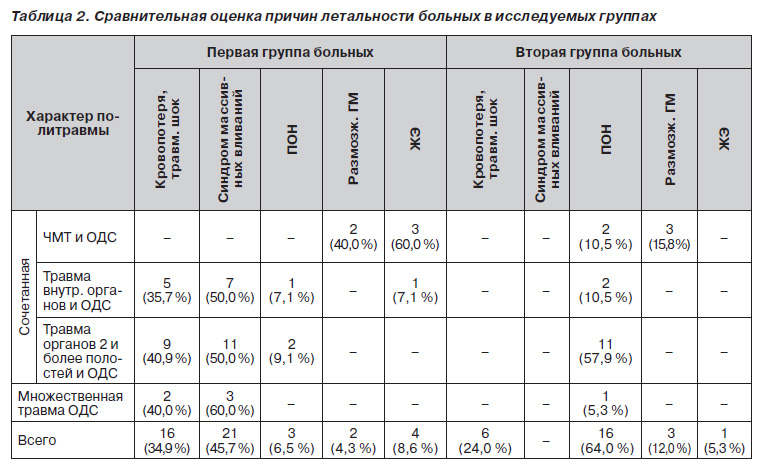

Эффективность используемой нами в последние годы медицинской технологии лечения больных с множественными и сочетанными повреждениями таза подтверждается и данными анализа причин летальности больных с политравмой, частью которой являются повреждения таза. Полученные данные представлены в табл. 2.

В первой группе больных (34,9 %) основной причиной летальных исходов были травматический шок и кровопотеря. У 45,7 % больных в результате попытки стабилизации нарушений гемодинамики за счет гемотрансфузий на фоне продолжающегося кровотечения причиной смерти стал синдром диссеминированного внутрисосудистого свертывания. По сути, эти причины подтверждают и убеждают, что без пломбирования костной раны оперативным сопоставлением костных фрагментов избежать продолжающегося кровотечения и формирования проблемных гематом не представляется возможным. Большинство больных первой группы (37; 80,4 %) погибли в первые сутки после травмы. Причиной смерти у 4 (8,6 %) больных была молниеносная форма синдрома жировой эмболии (ЖЭ), у 3 (6,5 %) — полиорганная недостаточность (ПОН).

Во второй группе наблюдений причинами летальных исходов, которые наступили в первые часы после поступления, у 6 (24,0 %) пострадавших были травматический шок, массивная кровопотеря, тяжелые травматические повреждения, у 16 (64,0 %) больных смерть наступила на 5–7е сутки от прогрессирования полиорганной недостаточности. Это свидетельствует о том, что выведение из шока не гарантирует сохранения жизни больного. Нужны дальнейшие исследования, уточняющие механизмы формирования полиорганной недостаточности.